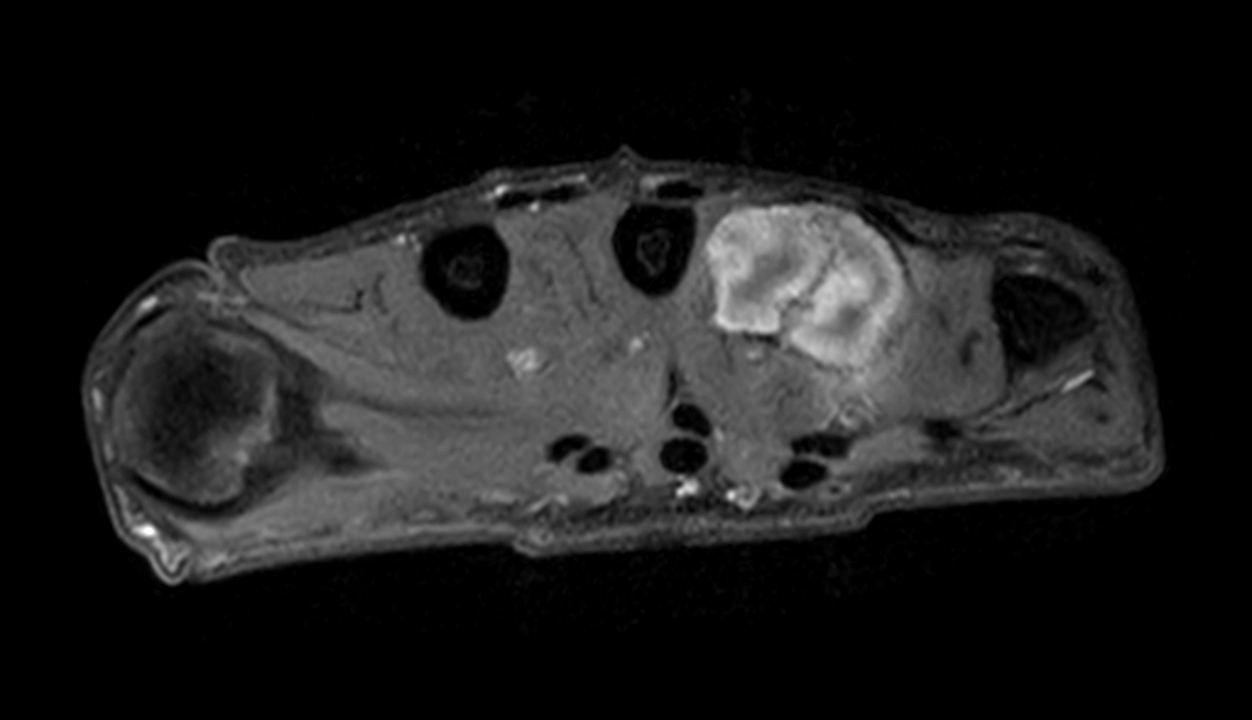

Axial PDw mDIXON XD TSE (Water only)

Axial PDw mDIXON XD TSE (In Phase)

Axial PDw mDIXON XD TSE (Partial FatSat)